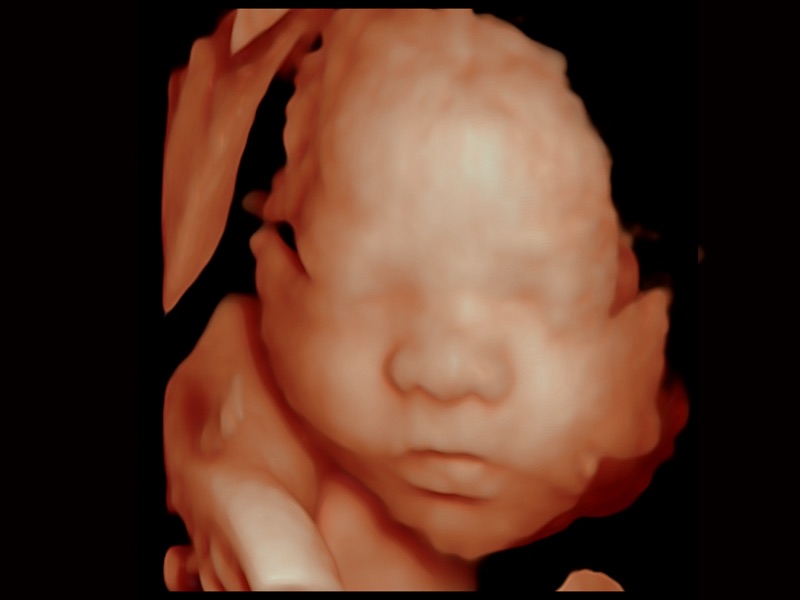

妇产科应用

三维光影成像技术采用新型的渲染方式,增强边缘信息,使得轮显示清晰完整,为临床提供丰富、直观的三维结构,提供临床诊断准确性。